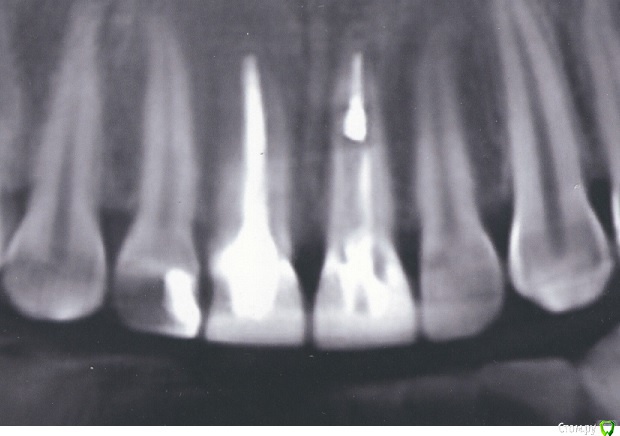

Opp80 Опубликовано 28 декабря, 2015 Автор Поделиться Опубликовано 28 декабря, 2015 (изменено) В продолжение о грустном, зуб левая единичка, уже изрезали мне десну теперь сзади, т.к. нет полож. динамики, сегодня сделал КТ, (сейчас выложу) врач предположил трещину или перфорацию, но на КТ ничего не увидел, единственное что предположил, что там где стоял предидущий СВШ (не по каналу) при повторном его прохождении "уступа" от него, могли сделать микро перфорацию, потому как перкуссия как раз с этой стороны, но он говорит что апекс не запищал, и крови не было, но я помню что гдето в этом районе я почуствовал укольчик, и это было до того как он прошел за апекс, я тогда еще испугался вдруг оно,перкуссия при фронтальном постукивании между мало-средне по чувству боли, при постукивании снизу менее выражена, все длится полгода с момента постановки коронок, сохраняется чувствительность.Сейчас он говорит делать ничего не будет тк нет воспаления, и посоветовал пойти на физ процедуры.Я чувствую что мне испортили полгода назад здоровый зуб, да еще и передний Изменено 28 декабря, 2015 пользователем Opp80 Ссылка на комментарий

Opp80 Опубликовано 10 января, 2016 Автор Поделиться Опубликовано 10 января, 2016 (изменено) Чувствительность уменьшилась, но не прошла, далеко не прошла, пульсация периодическая и с отдачей в этот сосочек в периоды активного движения, т.е например поход в магазин, но не каждый раз (отметил на фото), у зуба есть небольшая подвижность так сказала другой врач на консультации, она сказала что возможно от того что врач постоянно лазил под десну, связки нарушаются, чтото типа того, но по симптоматике похоже на трещину, мой же врач на последней консультации, сказал может перфорация, и сказал делать ничего не будет больше, я же все мучаюсь, коронка поменяла свое положение появилась небольшая диастема за все время вмешательств.Прилагаю также понорамный снимок, и если кто глубоко заинтересуется КТ https://yadi.sk/d/TAjzSbIumYiyoP.S. когда попросил врача рентгены то он резко негативно высказался о том что я хочу спросить все на форуме, мол там не мастера, чему удивился чего бояться то, но снимки сказал даст, но они не понадобились я сделал КТ.Напомню, коронки стоят с 29 июля примерно, так и мучаюсь Изменено 10 января, 2016 пользователем Opp80 Ссылка на комментарий

Opp80 Опубликовано 14 января, 2016 Автор Поделиться Опубликовано 14 января, 2016 (изменено) Сделал видео из КТ там видно уступ от старого штифта, хотя врач говорит апекс не пищал крови не былоhttps://yadi.sk/i/w9mc23axmyYuC только нажмите скачать , онлайн видео не проигрывает почему то, и снимок единиц отсканировал качество максимальное такой снимок Изменено 14 января, 2016 пользователем Opp80 Ссылка на комментарий

DmitrySH Опубликовано 14 января, 2016 Поделиться Опубликовано 14 января, 2016 Да, там очень тонко все, но признаков воспаления вокруг той зоны на кт не увидел 1 Ссылка на комментарий